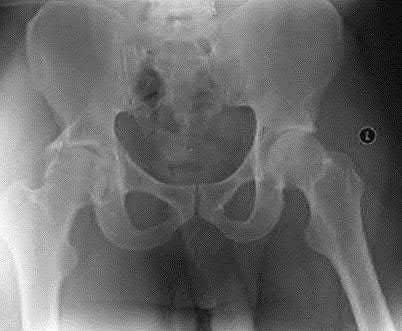

A 27 year-old patient sustains a fracture-dislocation of the acetabulum. Pelvic radiographs (Figures A and B) are taken at initial presentation and a CT scan (Figures C and D) is performed after reduction of the hip in the emergency room. What is the importance of the finding highlighted in the CT scan cuts?

The CT images shown in Figures C and D display significant marginal impaction of the joint surface.

Marginal impaction is common in posterior wall fractures and fracture-dislocations. Critical review of CT imaging of posterior wall fractures can help with preoperative planning for identifying impaction of the articular surface of the acetabulum. Restoration of the sphericity of the acetabulum to match that of the femoral head is important for successful outcome following ORIF of posterior wall fractures. A common surgical technique to accomplish joint surface restoration includes freeing the impacted articular segments, bone grafting of the void created to support the articular segments, and buttress plating of the posterior wall fracture fragments.

Figures A and B are radiographs of the posterior wall fracture and hip dislocation. They do not show the large amount of marginal impaction of the acetabular surface. Figure C (coronal reconstruction) and Figure D (sagittal reconstruction) point out a large a amount of marginal impaction of the acetabular. Note the disruption of the joint surface on the intact portion of the acetabulum.